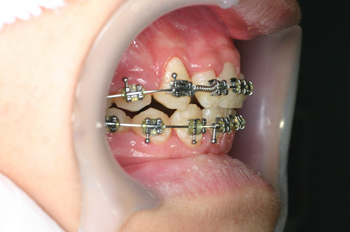

Process

顎が小さく歯が並びきらず、歯並びがデコボコになってしましっていましたので、拡大装置により、歯が並ぶスペースを作り、さらに余分な歯を取ることにより、全体のバランスを浴していきました。

治療の内容 歯列育形成による叢生の改善。

期間・回数 3年・35回(カウンセリング・検査含む)

費用 自由診療:歯列育形成 総額 570,000円(調整料34回分含む)税込627,000円